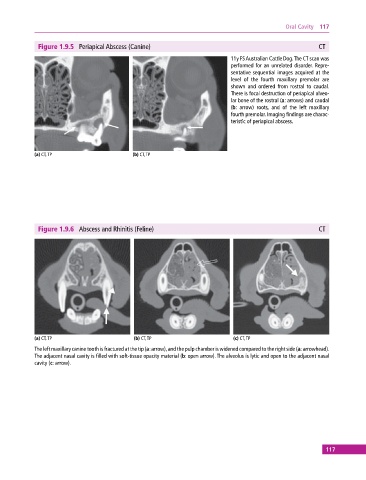

Figure 1.9.5 Periapical Abscess (Canine) CT

11y FS Australian Cattle Dog. The CT scan was

performed for an unrelated disorder. Repre

sentative sequential images acquired at the

level of the fourth maxillary premolar are

shown and ordered from rostral to caudal.

There is focal destruction of periapical alveo

lar bone of the rostral (a: arrows) and caudal

(b: arrow) roots, and of the left maxillary

fourth premolar. Imaging findings are charac

teristic of periapical abscess.

(a) CT, TP (b) CT, TP

Figure 1.9.6 Abscess and Rhinitis (Feline) CT

(a) CT, TP (b) CT, TP (c) CT, TP

The left maxillary canine tooth is fractured at the tip (a: arrow), and the pulp chamber is widened compared to the right side (a: arrowhead).

The adjacent nasal cavity is filled with soft‐tissue opacity material (b: open arrow). The alveolus is lytic and open to the adjacent nasal

cavity (c: arrow).